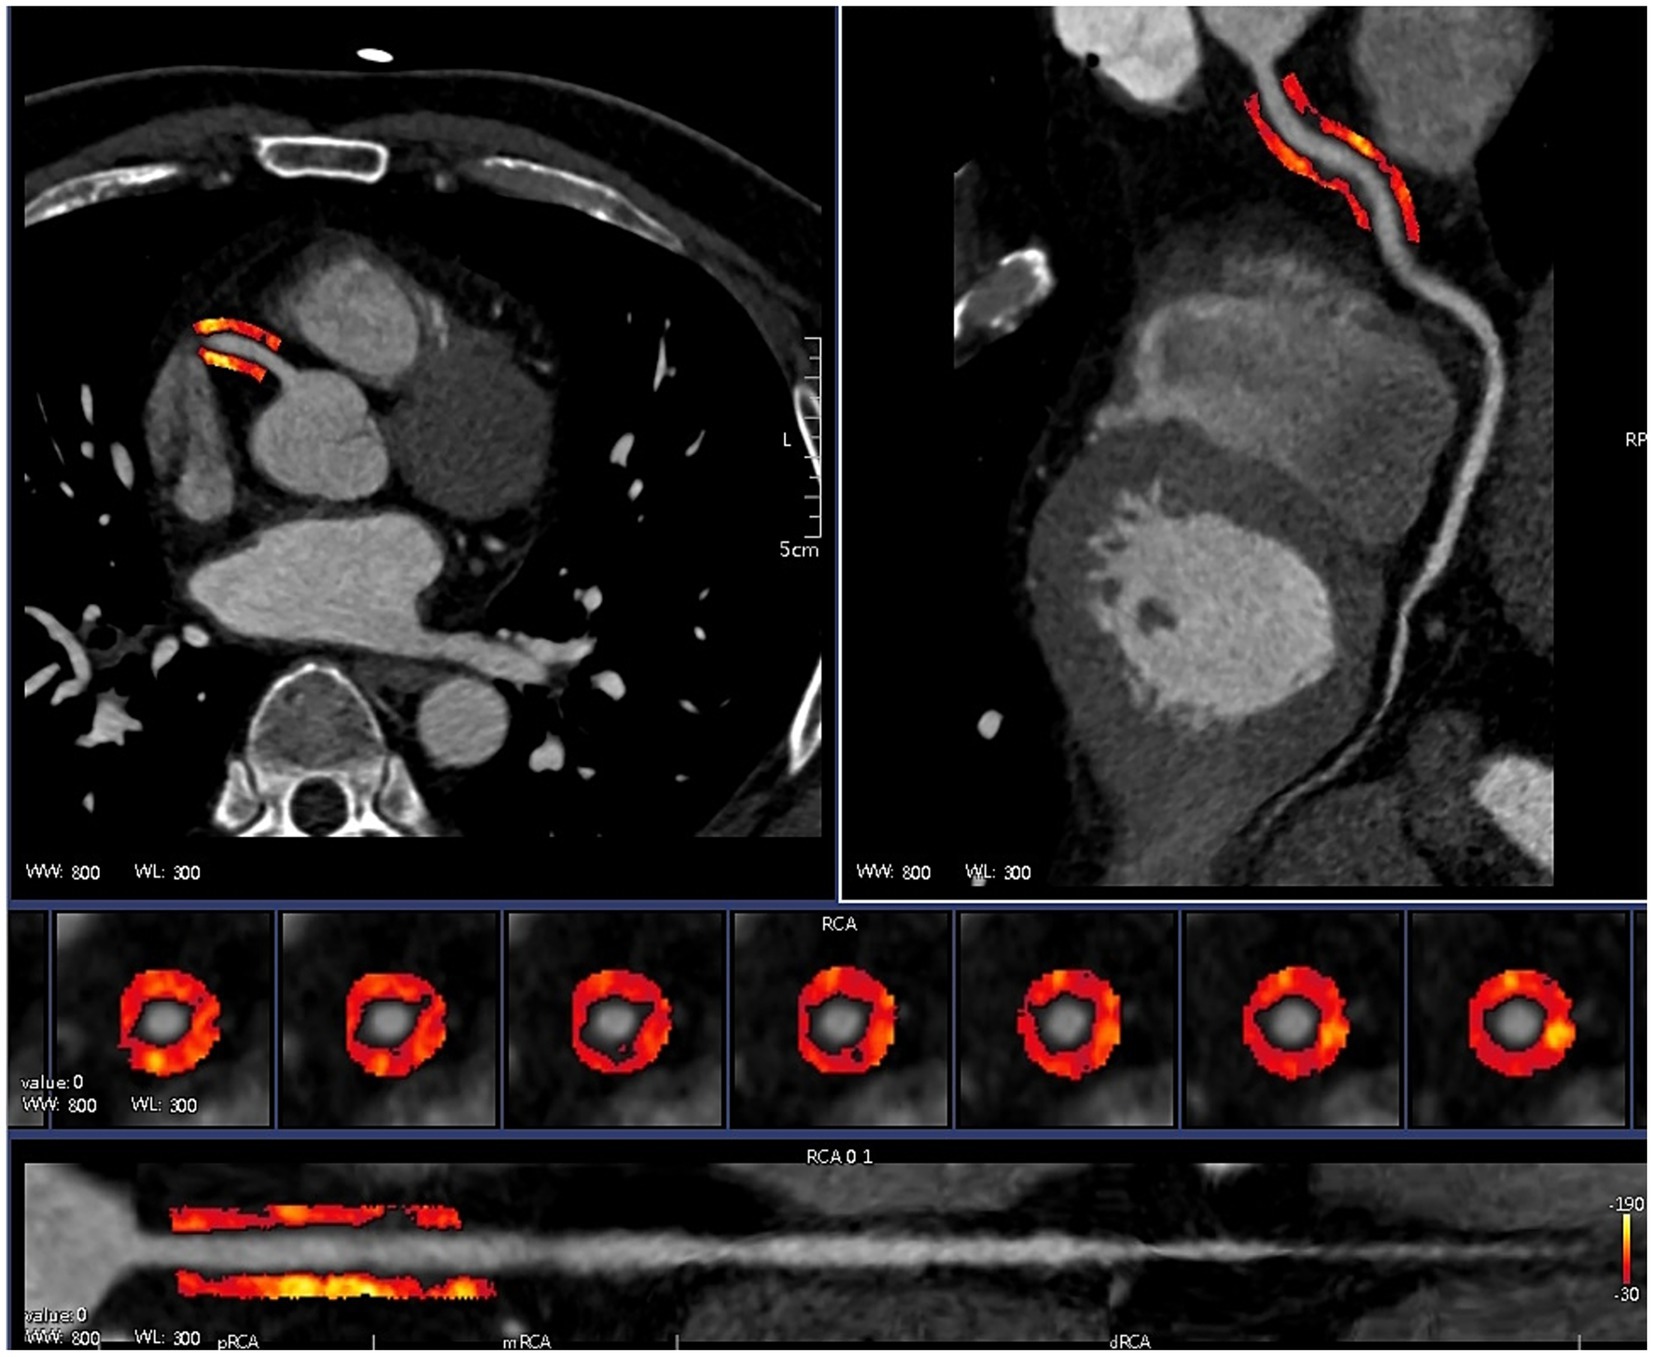

CCTA images of patients with CAD combined with T2DM were subjected to ROI segmentation of PCAT by selecting a 40 mm long and 3 mm wide section from 10 to 50 mm below the opening of the right coronary artery with a 1 mm gap around the coronary artery wall, using a Hounsfield unit threshold of −190 HU to −30 HU and using the centreline of the vessel as a baseline to ensure accurate segmentation of the PCAT (16) (Figure 3). The Perivascular Fat Analysis Tool software (UltraScholar’, Shukun Technology Co., Ltd., Beijing, China) was used to extract the PCAT radiomic features of the right coronary artery, which included first-order features, texture features, and shape features, and then, the original image was processed with seven filters, including the exponential, gradient, local binary (2D and 3D), logarithmic square and wavelet modes. This analysis integrates a comprehensive set of features. Features with the same radiomic feature values are eliminated by feature preprocessing, and the remaining features are subjected to feature preselection. Features with absolute values of Pearson correlation coefficients ≥ 0.9 were screened, and the remaining features were retained for analysis of CAD combined with PCAT radiomic features of T2DM patients for correlation analysis with genes.

Figure 3

Automatic drawing of PCAT.